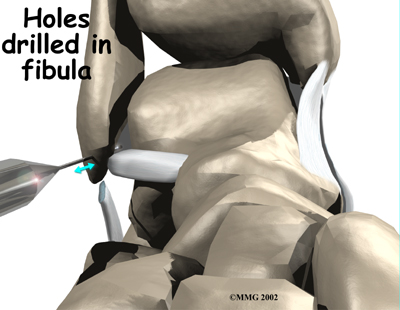

Holes are drilled along the lower end of the fibula bone, the small bone of the lower leg. The two ends of the cut ligament are overlapped and sewn together. The surgeon uses the drill holes in the fibula to hold the stitches to the bone.

The following images show each step of the ligament tightening procedure:

Step 2